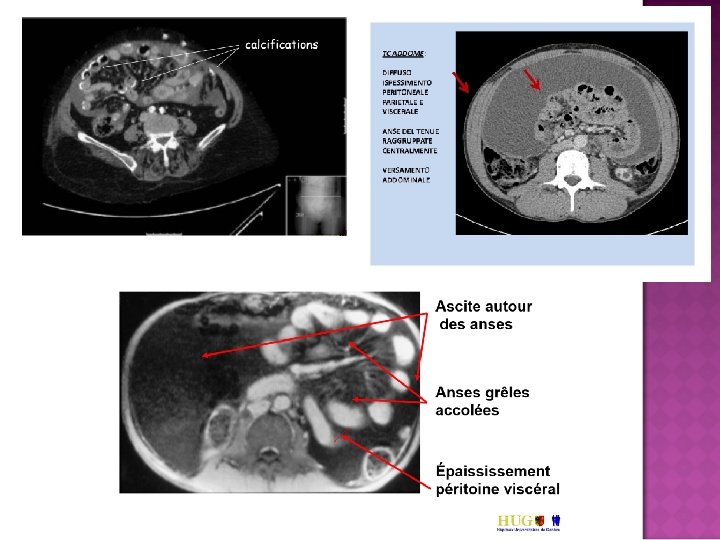

TDM abdomino-pelvien : Ascite abondante non cloisonnée, épaississement de la paroi du jéjunum et des premières anses iléales aspect subocclusif du grêle. coelioscopie

ascite épaississement de la paroi des anses digestives, encapsulation du péritoine Adhérences des anses digestives à la paroi abdominale antérieure avec dilatation Niveaux hydro-aériques ! Signes radiologiques inconstants ! anses digestives accolées au centre de la cavité abdominale

Corticothérapie 0, 5 mg/kg/jour Efficace ! Apyrexie en quelques jours amélioration progressive de l’état général, disparition de l’ascite, des troubles digestifs, du syndrome inflammatoire et de la résistance à l’EPO (Hb : 13, 8 g/d. L). TDM abdominale ( juillet 2000) disparition de l’ascite persistance néanmoins d’un épaississement de la paroi des anses jéjunales sans syndrome occlusif. Diminution progressive de la corticothérapie, arrêt en novembre 2000.